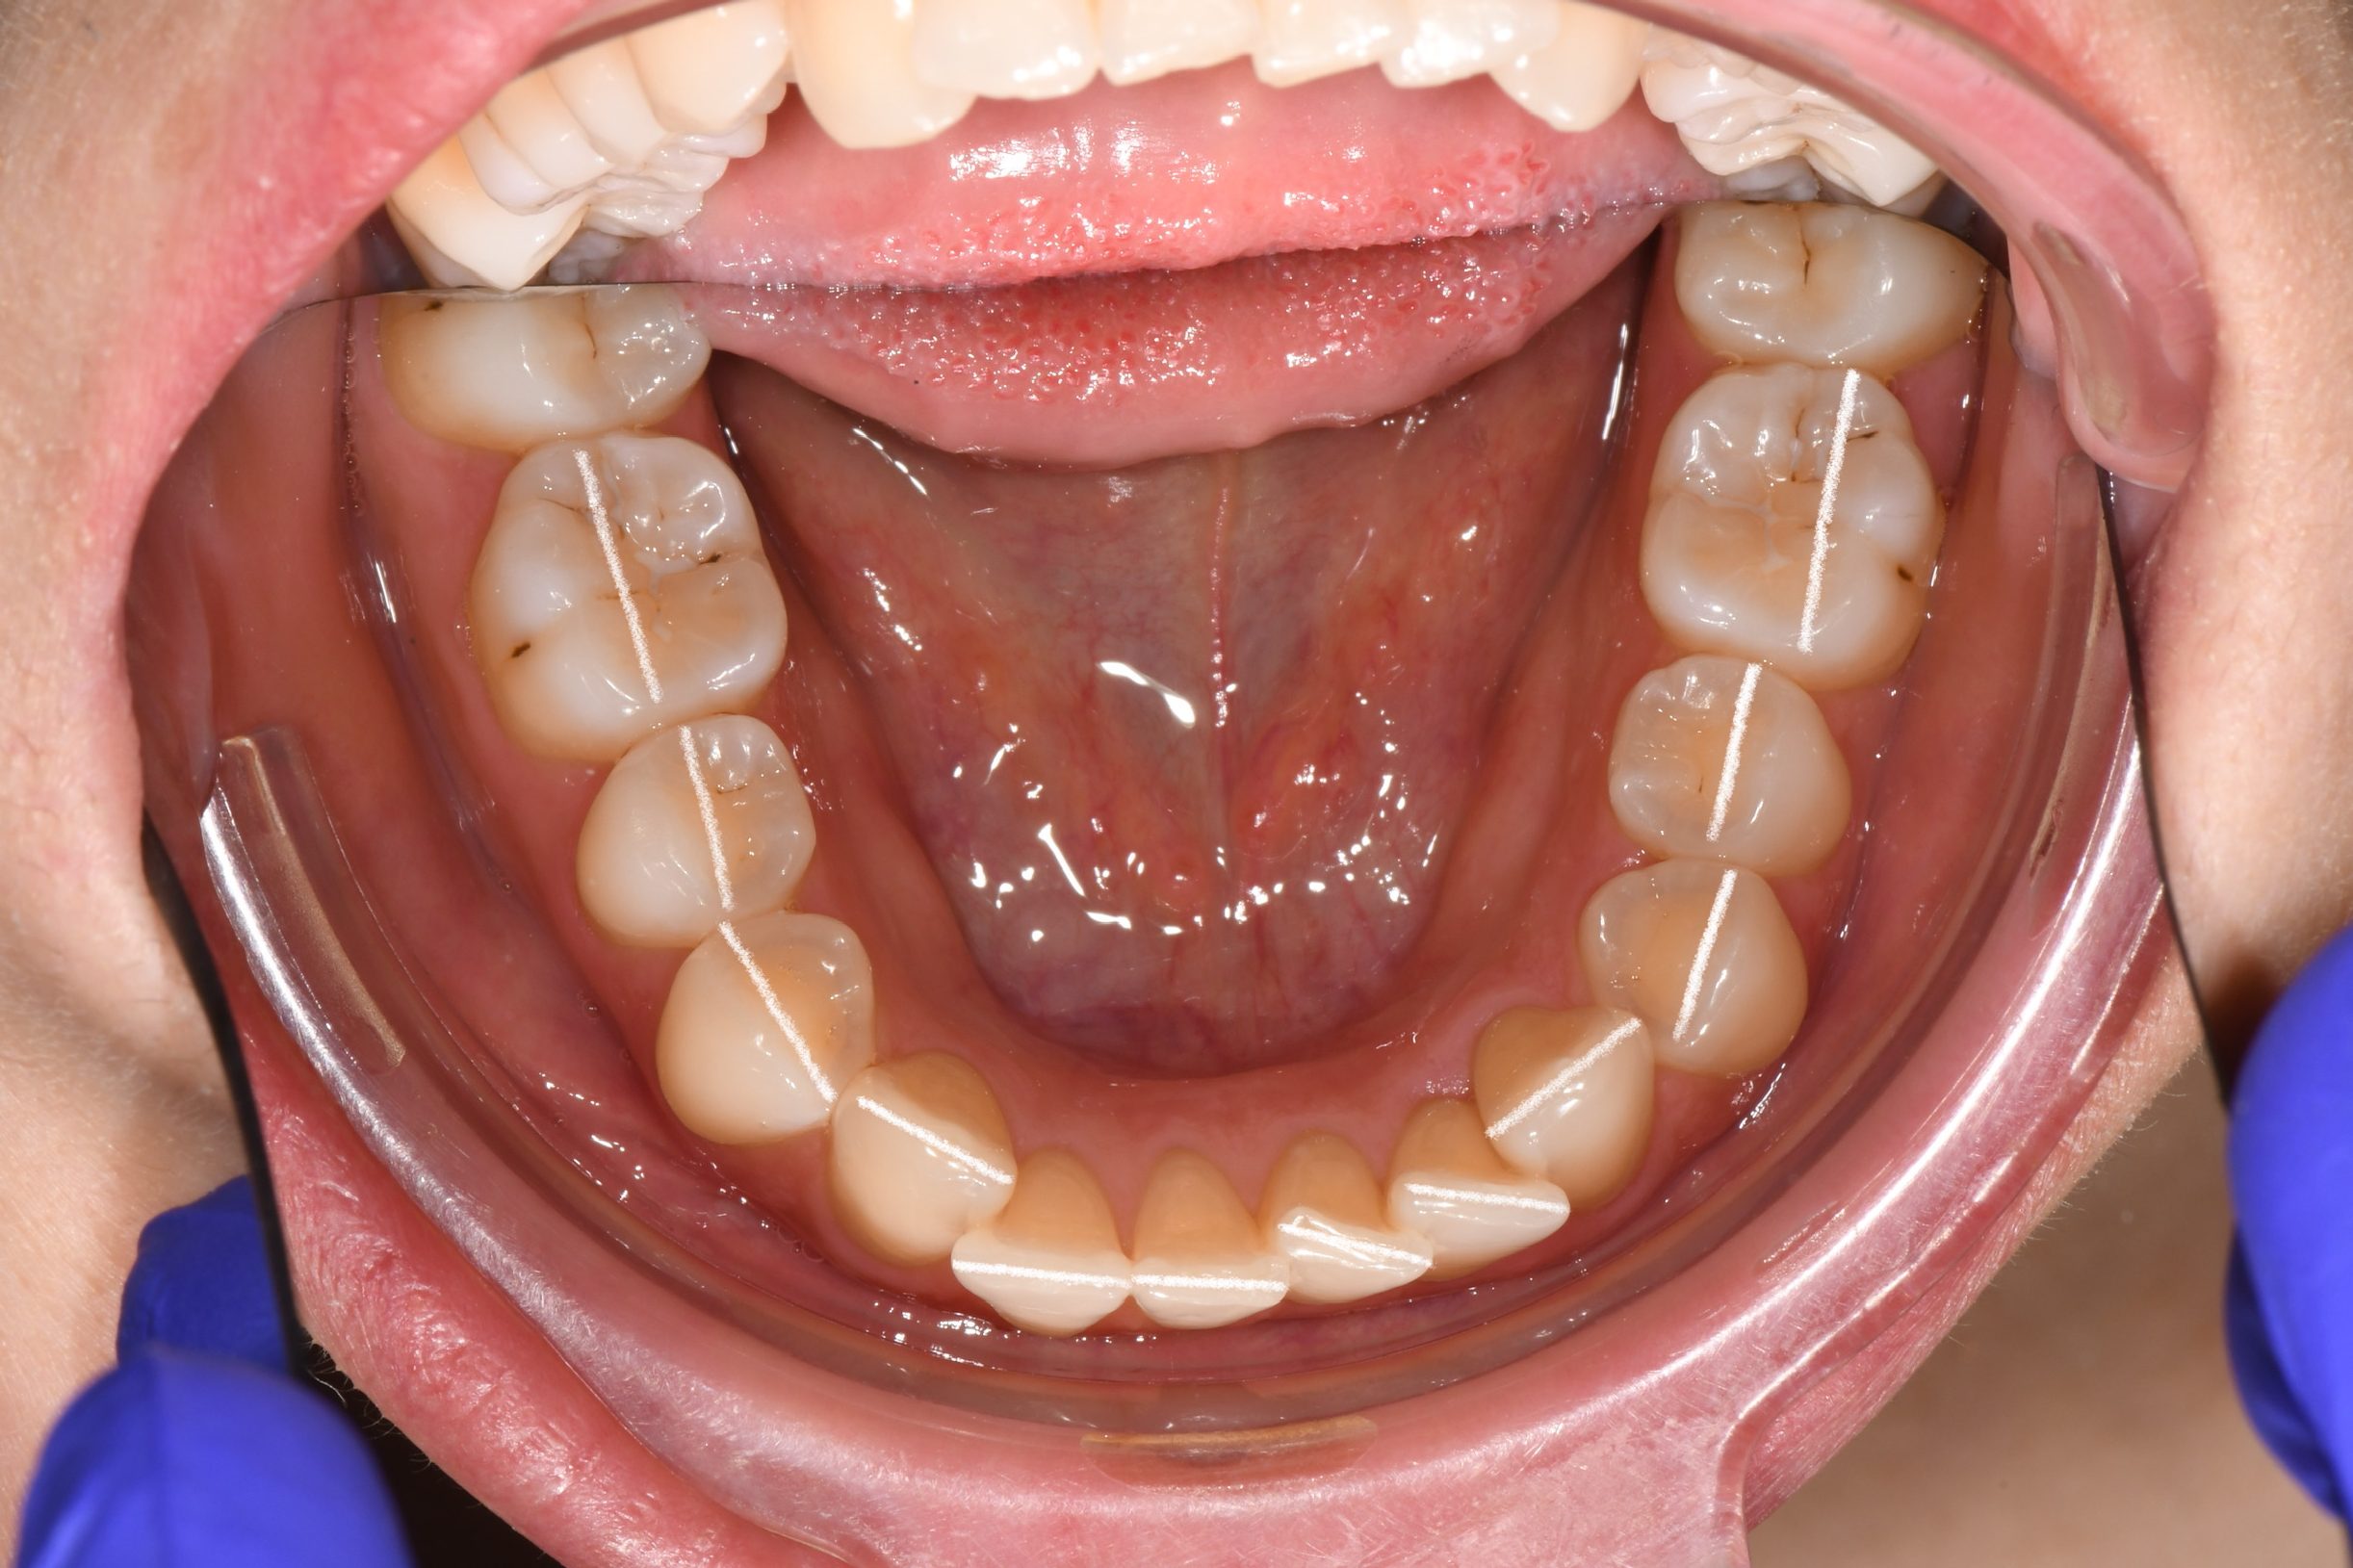

Az elmúlt évekből rengeteg szakmai referenciát tudnánk bemutatni, amelyek különböző fogszabályozási problémákat oldottak meg. Válogatva a több száz esetből, ezen az oldalon olyan képeket, információkat igyekeztünk bemutatni, amelyeknek a segítségével a jövőbeni pácienseinknek azt tudjuk üzenni: A Te fogsorod is lehet gyönyörű!